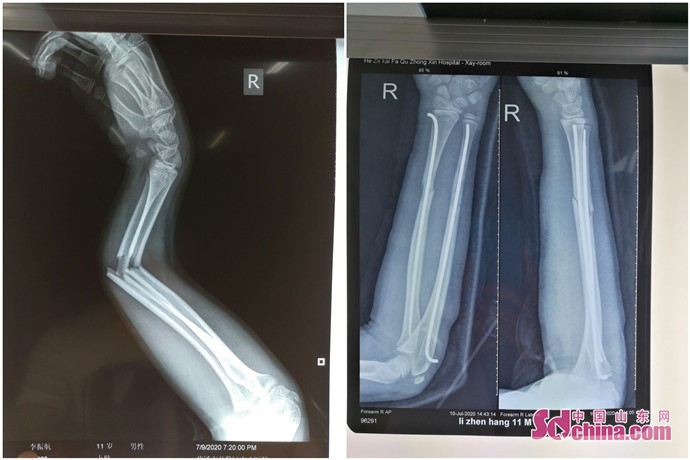

微创弹性髓内针内固定术 治疗长骨骨折

菏泽开发区中心医院:儿童骨折别大意 及时就医正确处理

小儿骨折保守治疗(二)

儿童骨折#髓内钉不可刺激皮肤,不可压迫生长板,不可影响关节 - 抖音

经过1个月的治疗后复查片可见骨折端对位对线良好,可见大量骨痂生长.